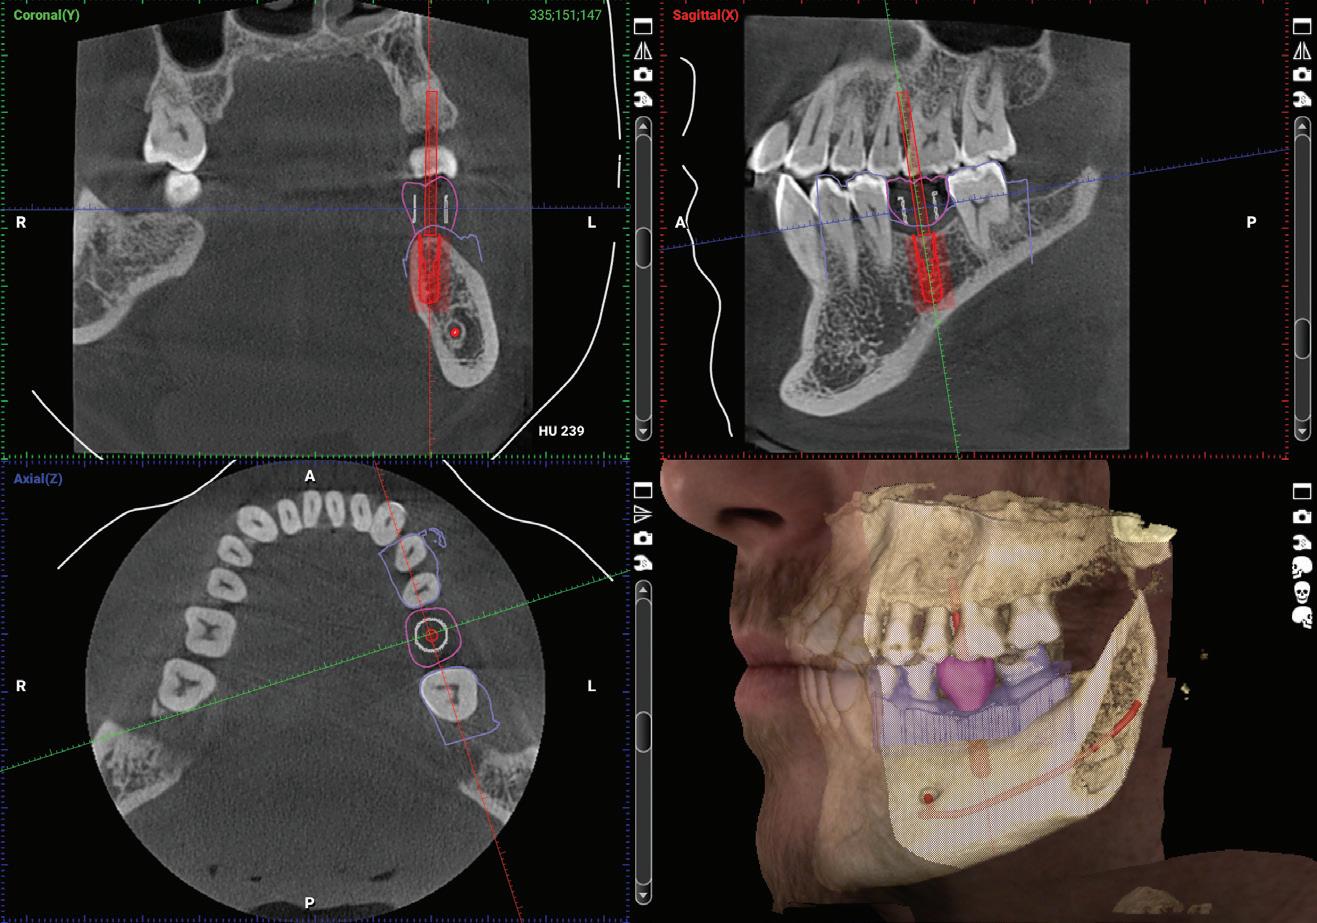

CBCT imaging is the most comprehensive tool for adding procedures and efficiencies by providing predictable diagnostics. For example, with the advancement of low-dose 3D imaging, the concept of a 3D PA (replacing a PA for diagnosis) is often a better clinical choice.

According to a study from Clinical Research 2017, 50% of small volume scans found asymptomatic abnormalities. Studies of large FOV CBCT scans show the prevalence of incidental finding to be greater than 90%. During 3D training, we often find these infections and other asymptomatic issues on the scans. The direct connection between oral health and overall systemic health emphasizes the importance of early diagnosis.

Surgical guides are amazing tools to overlay your cone beam (hard tissue) with your IO scan (soft tissue) for restorative and implant-driven surgical planning. With this technology, you can digitally plan your case and have a surgical guide giving you the confidence to add these procedures to your own practice.

JMartin@BurkhartDental.com 253.273.5890 Joe Erbaugh Eastern Washington Clinical Digital Specialist JErbaugh@BurkhartDental.com 503.341.8730 STL integrated with DICOM for surgical guide design BurkhartDental.com